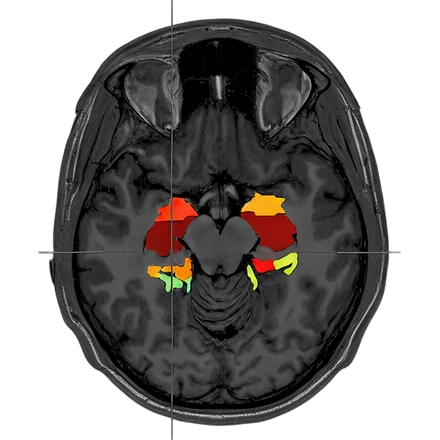

fMRI

Functional (fMRI)

3.0T

0.5T

Images from: Halder et al., Investigating the feasibility of resting state functional MRI with GRE EPI on a high performance 0.5 T Scanner, processed using GraphICA, an asset of Brainet-Brain Imaging Solutions Inc.